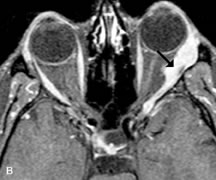

Cystic Lesions

Dermoid cysts appear as rounded, well-defined lesions typically contiguous with an orbital bony suture. The high-intensity signal on T1-weighted images is attributed to the sebaceous-produced lipid contents (Fig. 18).31,50 Mucoceles may demonstrate a hypointense or hyperintense signal on MR images, depending on the concentration of proteinaceous or inflammatory fluid components. The integrity of the bony walls of the expanded sinus cavities cannot be assessed on MR as well as by CT.37,50,55,56 A high-signal intensity on Tl- and T2-weighted images is characteristic of orbital chronic hematic cysts because of the blood-breakdown products within the cysts.57

Fig. 18. A. T1-weighted, (B) T2-weighted fat-suppressed, and (C) T1-weighted fat-suppressed MR scans demonstrate a small dermoid cyst arising near the palpebral portion of the lacrinal gland (arrows). The lesion is similar in signal intensity to fat on the T1-weighted scan (A) consistent with a high adipose tissue content. The lesion shows fat-suppression and low signal intensity on the two fat-suppressed sequences (B and C) confirming its high lipid content.